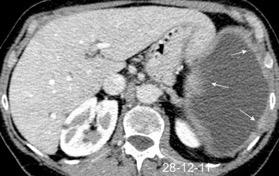

Marzo 2014: Perforación longitudinal distal secundaria a episodio de vómito (síndrome de Boerhaave). Derrame pleural izdo. que evoluciona a empiema.

Wang C-T et al. Tension hydropneumothorax in a Boerhaave syndrome patient: A case report . World J Emerg Med, 2021. Katabathina V et al. Nonvascular, nontraumatic mediastinal emergencies in adults:a comprehensive review of imaging findings. Radiographics. 2011.